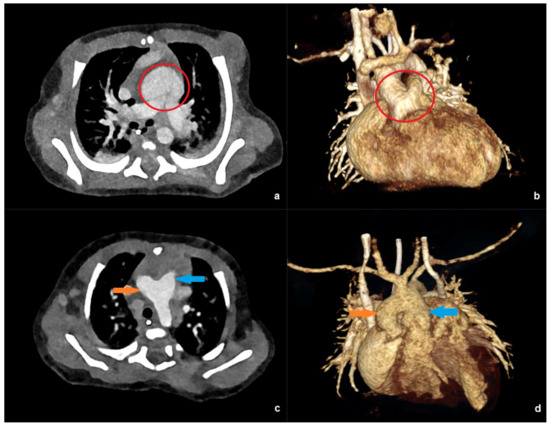

Figure 3 shows examples of low-dose PC-CT examinations in two of the youngest patients in our collective.

Figure 3.

PC-CT of a 10-day-old patient with an effective dose of 0.19 mSv: (a) transverse maximum intensity projection, and (b) 3D anterior reconstruction demonstrating a common arterial trunk (red circle). PC-CT of a 59-day-old patient with an effective dose of 0.41 mSv: (c) transverse image, and (d) 3D anterior reconstruction showing a large aorto-pulmonary window with a connection between the pulmonary trunk (blue arrow) and the ascending aorta/aortic arch (orange arrow).